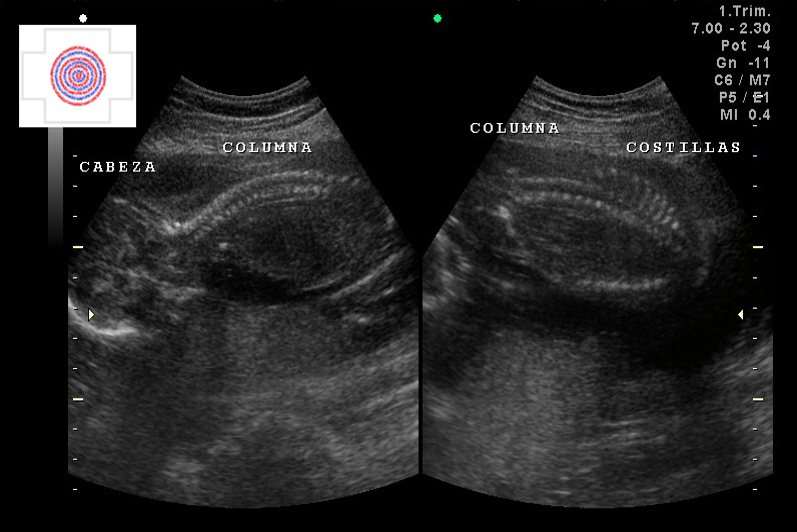

2D, CABEZA, COLUMNA, COSTILLAS